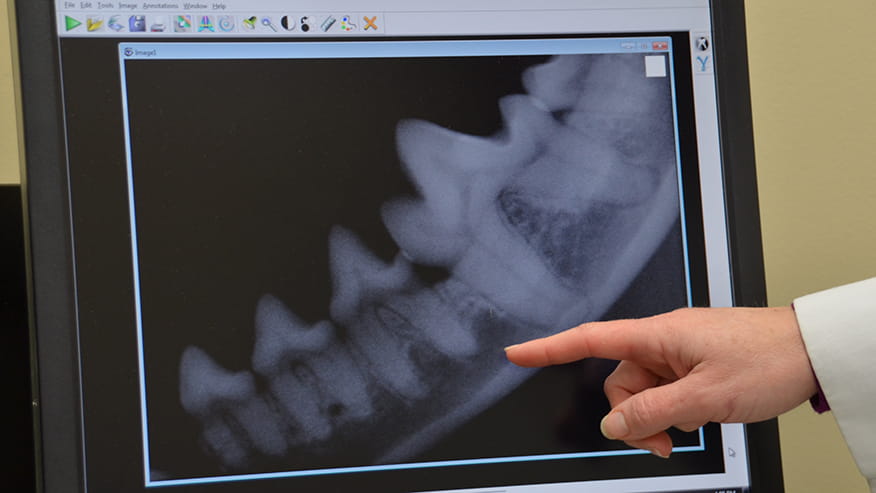

Dental X-Rays allow us to see the tooth roots under the gum line to determine if there are any diseased teeth and the best treatment options.... Read more